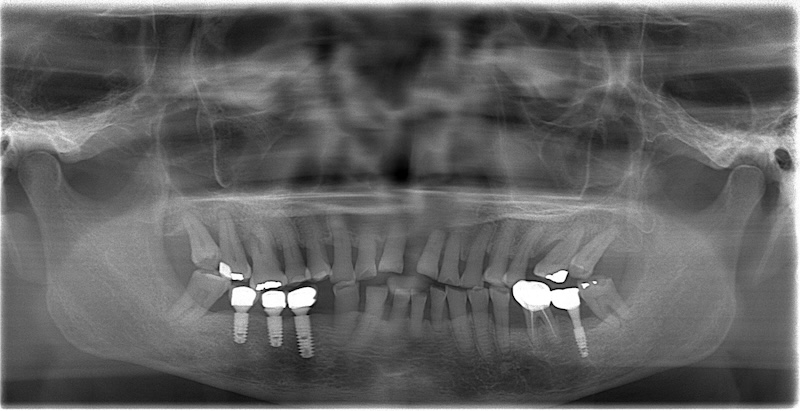

初步進行口內檢查,搭配環口式 X 光片和左上正中門齒的局部 X 光片評估。我的診斷是全口嚴重牙周病,且左上正門齒的齒槽骨破壞已經超過牙根尖端,屬於牙周病的無救牙,位置也己經很不理想,不得已只能建議拔牙。

嚴重牙周病拔牙與缺牙重建方式評估

一般來說,這類情況會先治療牙周病到初步穩定的程度,再利用矯正的方式把牙齒排整齊,最後可能透過植牙或其他方式來修復缺牙。不過考量到 Ms.D 是從外地來,且是年紀較大的長者,治療期間不適合太長;再加上牙周病導致牙齒鬆動,種種都是不利於矯正的因素,因此我們可以說,矯正治療是需要被排除的。